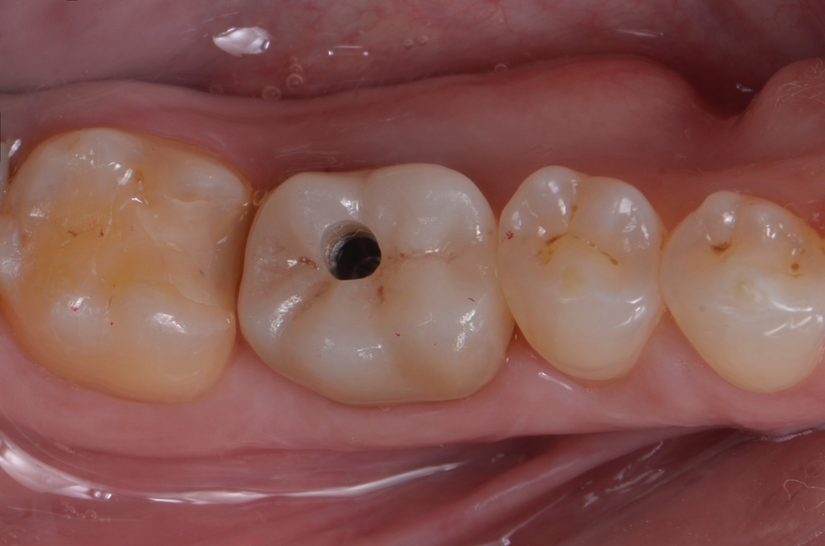

O paciente apresentou fratura vertical mésio-distal no elemento 46. Foi planejada a exodontia minimamente traumática e instalação imediata do implante Maestro Superiore (Implacil Osstem) utilizando uma guia prototipada. Após a exodontia, o implante foi instalado seguindo o protocolo de cirurgia guiada. O GAP vestibular foi preenchido com o Extra Graft. Um cicatrizador personalizado impresso com haletas facilitadoras foi capturado com resina flow e instalado. Após 30 dias, foi realizado escaneamento indireto para obtenção do perfil de emergência, utilizando protocolo digital com sobreposição do cicatrizador escaneado para confecção da coroa definitiva em zircônia policristalina estabilizada por ítria.

Escaneamento digital e reabilitação com coroa definitiva

O uso de cicatrizadores personalizados, especialmente confeccionados por impressão 3D, tem ganhado destaque por permitir a conformação tecidual progressiva, facilitando a reprodução do perfil de emergência no fluxo digital6,7. A captura do cicatrizador com haletas de retenção com resina flow e seu posterior escaneamento são etapas críticas para assegurar a fidelidade da transferência do perfil de emergência e garantir um planejamento restaurador mais previsível8.

Neste caso, a sobreposição digital entre o cicatrizador escaneado e o desenho da coroa possibilitou comparar perfis de emergência com excelente adaptação clínica, contribuindo para um resultado estético e funcional adequado.